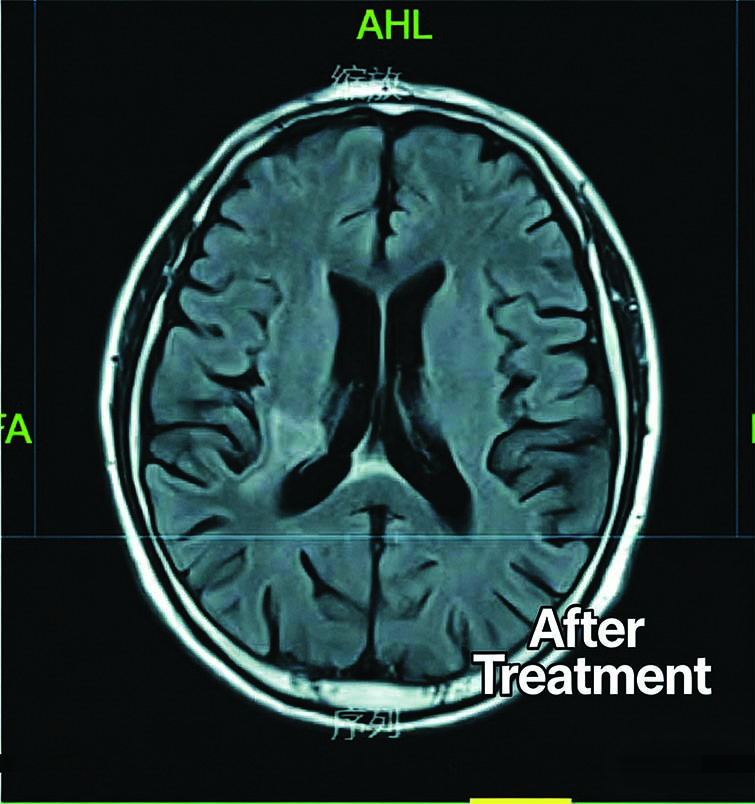

Before Treatment

After Treatment

Patient: 67-year-old male

Diagnosis: Secondary Malignant Brain Tumor

Treatment:lnitiated CyberKnife radiotherapy on August 3, 2020

Radiation dose to 95% GTV: 15 Gy in 3 fractions (5 Gy per fraction) Outcome:lmaging review three months later shows a significant reduction in the tumor size compared to previous scans.